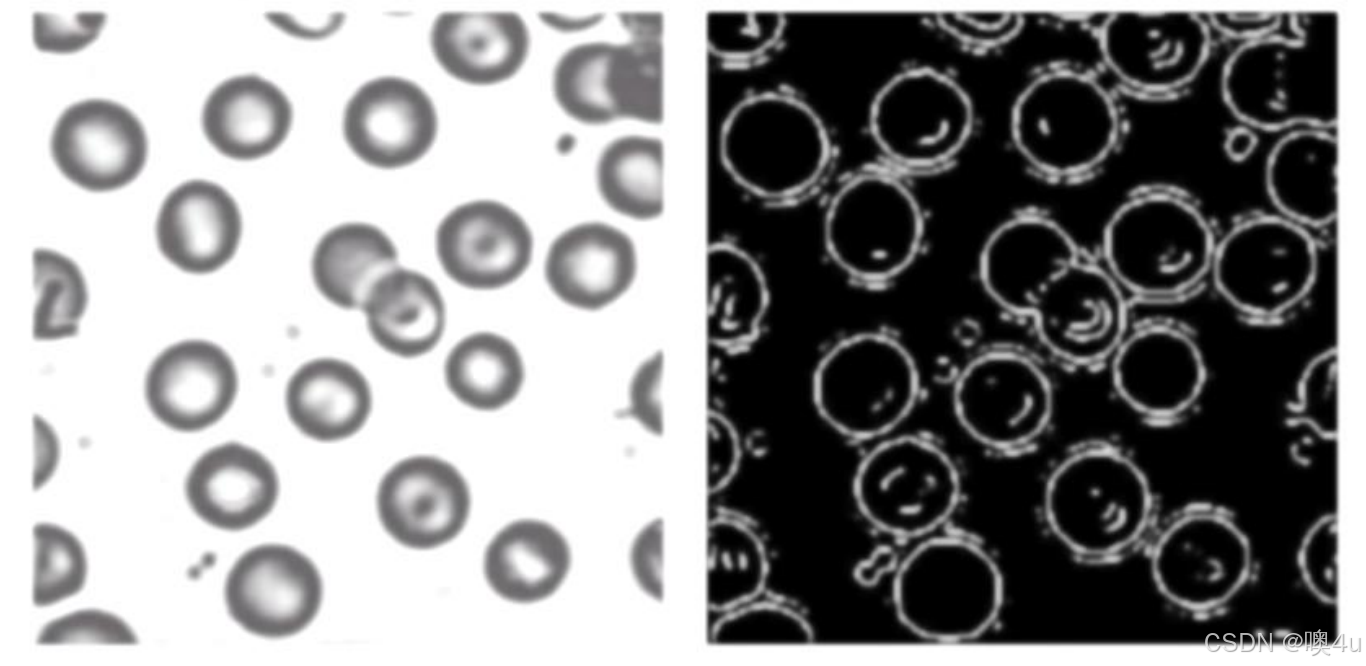

例:如何求单位体积内,红血球细胞的个数;红血球细胞的直径?

- 1. 图像增强:首先对左侧的原始图像进行图像增强,目的是提高红血球的边缘清晰度,从而便于后续的边缘检测。可以使用以下方法:

- 对比度增强:增强图像的对比度,使红血球边缘更加清晰。

- 平滑滤波:去除图像中的噪声,避免噪声干扰边缘检测结果。

- 锐化处理:增强红血球边缘的细节,使得细胞轮廓更加明显。(具体见下)

- 2. 边缘检测:增强后的图像可以通过边缘检测算法提取红血球的边缘。通过边缘检测得到的结果类似于右侧图像,其中红血球的边缘被清晰地标出。常用的边缘检测方法有:

- Canny 边缘检测:一种常用的边缘检测算法,可以提取出红血球的清晰边缘。

- Sobel 算子:可以增强水平和垂直方向的边缘,便于检测圆形的边界。(会在后续篇章中有具体涉及)

- 3. 轮廓提取和形态学操作:边缘检测得到二值图后,可以进行一些形态学操作来进一步处理:

- 闭运算:填补红血球轮廓中的小空隙,确保边界完整。(见下《图像运算》)

- 连通域分析:将各个红血球的轮廓分离开来,以便后续计数和测量。(在《1.数字图形基础》中有具体介绍)

- 4. 计算红血球数量和直径

- 数量计算:对每个连通区域(红血球)进行标记计数,统计出单位面积内的红血球数量。

- 直径测量:对于每个红血球轮廓,可以测量其外接圆的直径,获得红血球的平均直径。